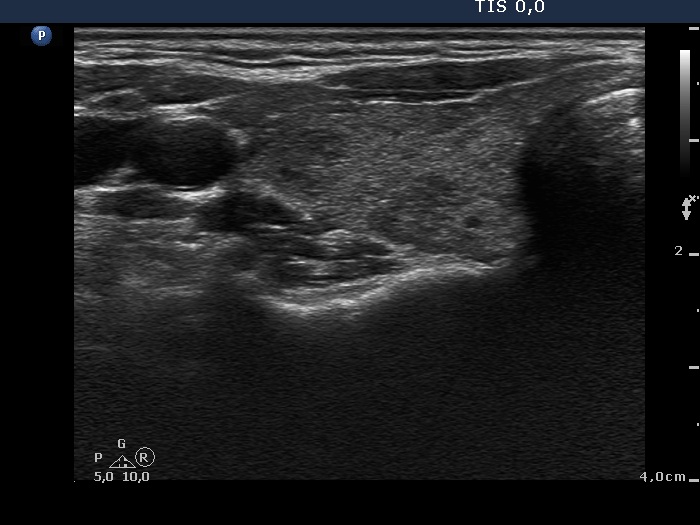

Discrete lesion or nodule in Hashimoto's thyroiditis - case 9 (644)

Thirteen months after the first examination (ultrasonographic picture 2)

Right lobe, another transverse scan. There are several hypoechogenic islets within the echonormal backgound.